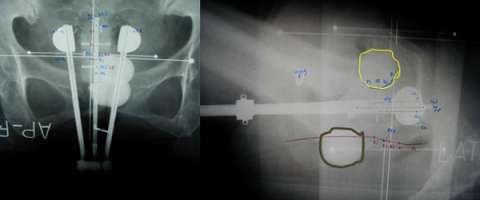

In the images below for example on the right is an anterior-posterior view of a vaginal applicator inserted in the vagina. You can see the cylinder pushing up against the top of the vaginal apex. You can't see the outline of the entire bladder and rectum but one way to approximate them is to place foley catheters in the bladder (yellow outline) and the rectum (brown outline) so they can be visualized.

Our approach at UCLA is to do 3D based instead of 2D based planning for these cases as well. Once again one can immediately appreciate how much additional detail in the anatomy and distribution of the radiation dose can be appreciated on the CT scan versus the X-ray.

ovoid applicator

Example of 2D based planning using a tandem and ovoid applicator

axial image

An example of 3D based planning with an axial image on the left and a coronal image on the right.